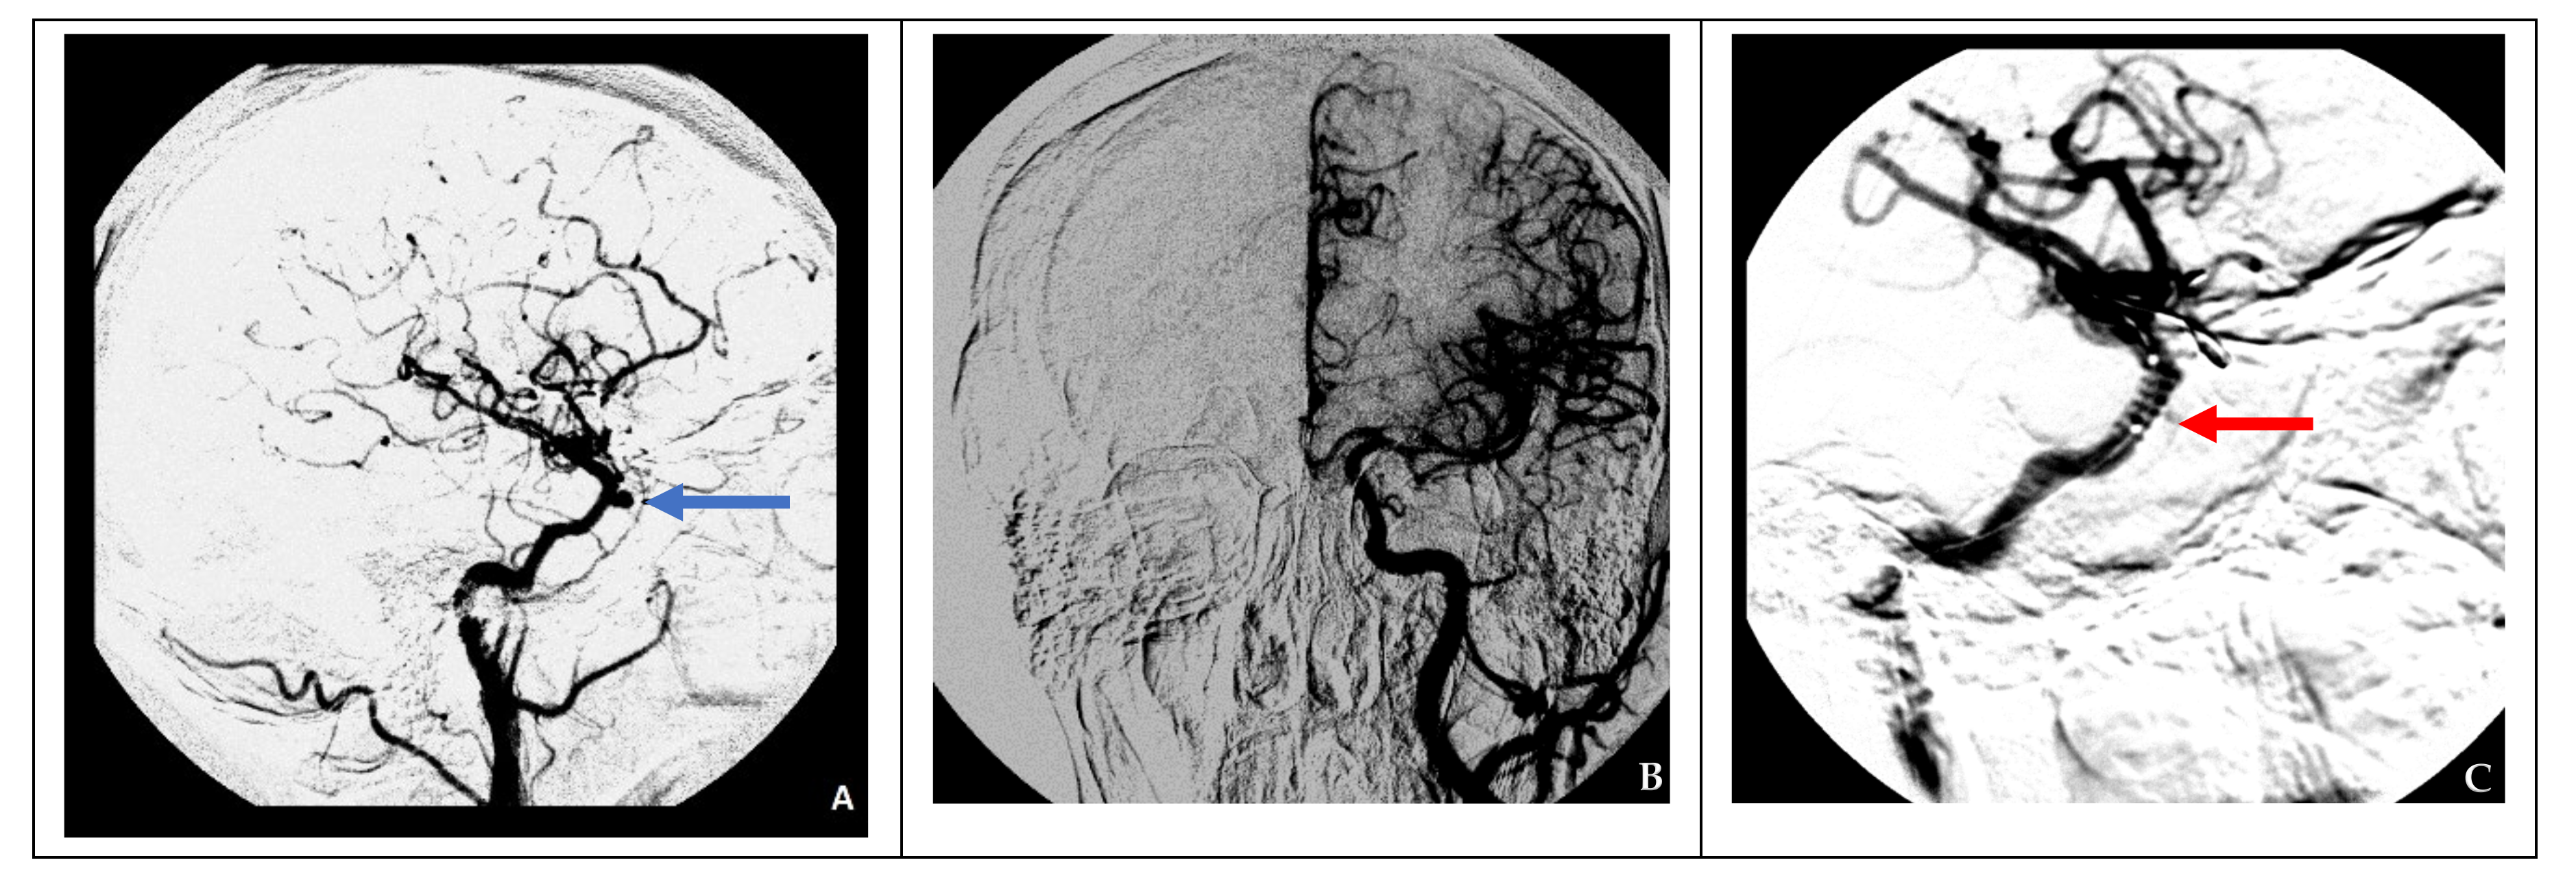

In cases of adequate collateral blood flow, endovascular occlusion at the ICA injury site using balloons in two cases and microcoils in three cases was performed (Figure 2).

Figure 2. Endovascular surgical treatment in cases with good collateral circulation (clinical case 2). (A) A false aneurysm in the area of the cavernous segment of the right ICA (indicated by the blue arrow), (B) cerebral angiography of the left ICA demonstrating good collateral blood flow to the contralateral side, and (C) occlusion of a defect in the right ICA using two balloons (indicated by red arrows).